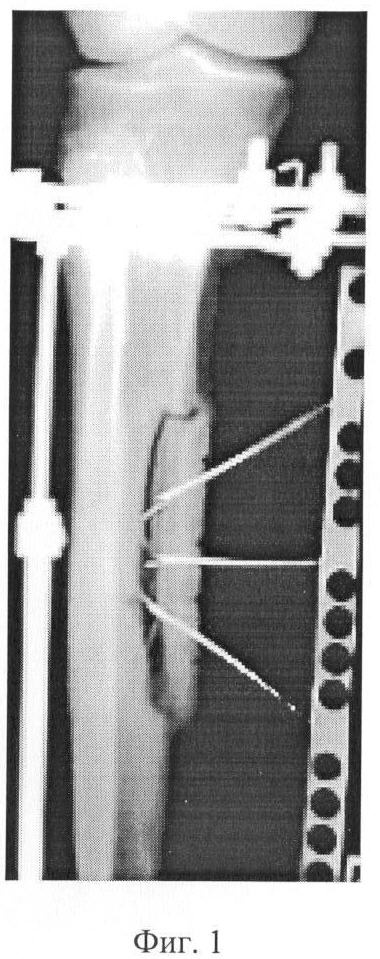

Фиг. 1 – рентгенограмма голени больного в процессе лечения хронической артериальной недостаточности путем дозированного перемещения сформированного продольного отщепа правой большеберцовой кости после предварительной туннелизации ее диафизарного и метафизарного отделов.

В ходе операции, после анестезии и обработки операционного поля, больному первоначально произвели туннелизацию диафиза и обоих метафизов правой большеберцовой кости, сформировав 6 сквозных туннелей на протяжении диафизарой части и по два глухих туннеля со стороны костномозговой полости – в обоих метафизах. Затем, после наложения аппарата для чрескостного остеосинтеза на голень, через разрез мягких тканей сформировали продольный отщеп большеберцовой кости величиной 7 см, который фиксировали тракционными спицами. Операцию завершили выполнением контрольной рентгенографии и стабилизацией систем аппарата.

В послеоперационном периоде, начиная с 5 дня, производили дозированное – с темпом 0,5 мм в сутки – смещение сформированного отщепа (Фиг. 1). Продолжительность тракции составила 28 дней, после чего системы аппарата стабилизировали. Срок последующей фиксации в аппарате составил 35 дней. К указанному сроку рентгенологически выявлена картина консолидации большеберцовой кости и отщепа костным регенератом, который затем полностью оссифицировался (Фиг. 2, 3). Это позволило демонтировать аппарат на 15-20 дней раньше, чем у пациентов с аналогичной патологией при стимуляции кровоснабжения ишемизированных конечностей, методом чрескостного остеосинтеза, у которых консолидация кости отмечается лишь к 45-60 суткам.